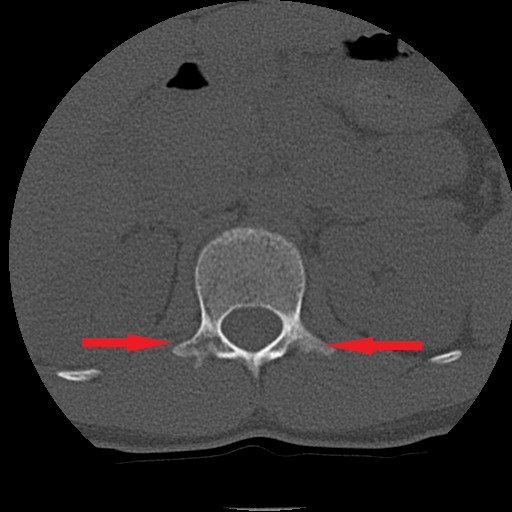

4月 MRI検査にて腰椎分離症の診断。コルセット装着の保存療法にて安静加療の指示。

6月 再検査。腰椎分離症の進行が見られた。

9月 再検査。変化なし。ボルトで脊椎を固定する手術(脊椎固定術)を打診される。

10月15日 再検査にて分離部位の癒合が認められるとの所見。

11月15日 再検査にて更に分離部位の癒合が認められるとの所見。現時点で腰痛や下肢疼痛など症状の再発は無し。

今回ご紹介する症例は、半年もの間一向に改善しなかった腰椎分離症がわずか1ケ月半の間に、しかも4回の施術で劇的な改善が見受けられたことについて、病院での一連の検査が終了した後に受療者の保護者より病院での検査記録の提供を受け、発症から治癒に至るまでの詳細について時系列でお伝えするものす。また、この症例はこれらの画像提供を受ける2ヶ月前の段階で既に筋肉反射テストにより損傷部位を正確に特定し、骨の癒合を促す施術を行った結果です。この目まぐるしい回復に専門医も只々驚愕しきりだったとか。本人は手術を受けるつもりでいたようですが、我が子の体にメスを入れることを良しとしなかった母親の慈愛が正しい選択に向かったのでしょう。CTやMRIは最先端の医療検査と思われがちですが、残念ながら損傷が分ったとしてもそこには回復させる術はありません。正しい検査のみが治癒の道筋を着けることを可能とします。体は常に自力で治ろうとして様々な症状を発現しています。体の訴えに耳を傾ける時、きっと自身の治癒力が成せる奇跡のような回復劇が待っていることでしょう。当院の施術には何のリスクもありません。手術を受ける前に是非ご相談ください。